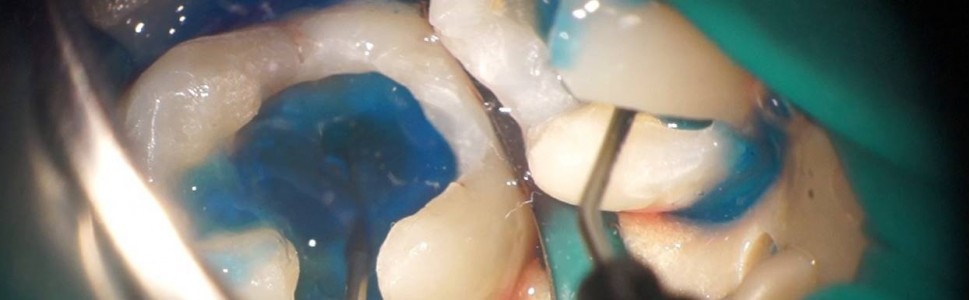

W pracy omówiono zasady działania dezynfekcji fotoaktywnej wraz z mechanizmem aktywacji tlenu molekularnego na poziomie komórek bakteryjnych. Na podstawie własnych przypadków klinicznych przedstawiono możliwości zastosowania PDI (photodynamic inactivation) w endodoncji, periodontologii oraz implantologii.

The study describes the principles of action of photo activated disinfection together with the mechanism of activation of molecular oxygen at the level of bacterial cells. On the basis of personal clinical cases there is a presentation of the use of PDI (photodynamic inactivation) in conservative dentistry, endodontics, periodontology and implantology.